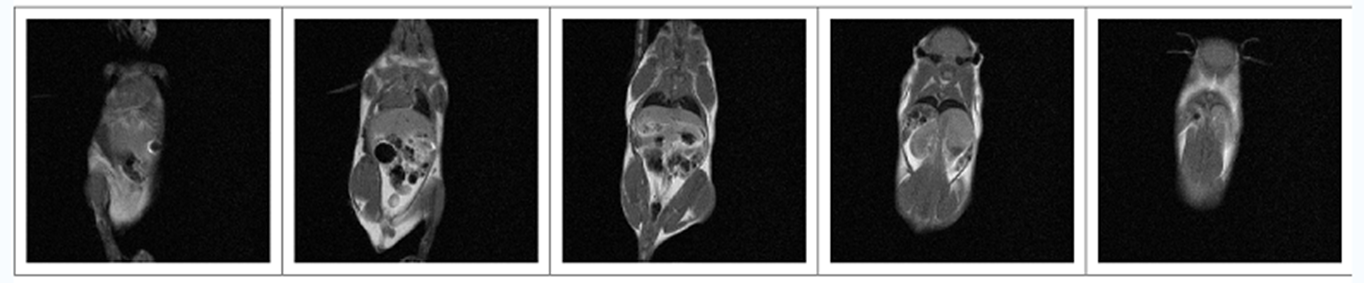

核磁共振成像_简介(一)

核磁共振小知识分享 |